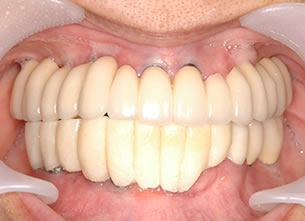

症例1 : 上下顎無菌顎症例

69歳、男性。

• 上顎は両側サイナスリフトと同時に即時荷重を行った。

• 下顎は抜歯即時埋入即時荷重を行った。

• 最終補綴物は、チタンのP.I.B.とM.B.のコンビネーションで修復した。

• 本症例の要旨は第39回日本口腔インプラント学会(大阪)にて症例報告した。